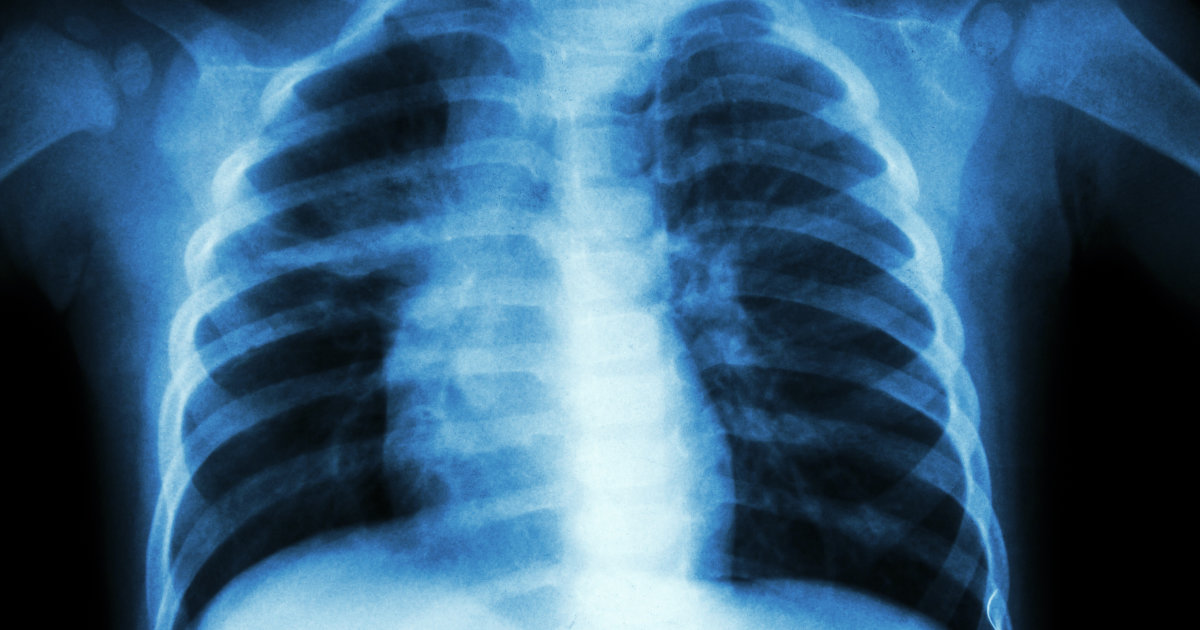

Tuberculosis

Tuberculosis is a serious infectious disease caused by a bacteria called Mycobacterium TB. This bacteria usually has a primary effect on the lungs, but it can cause damage to other parts of the body as well. There are a couple of ways tuberculosis can cause hypopituitarism. Tuberculoma or a firm mass of tubercles that forms from tuberculosis can have the same effects on the pituitary gland a benign tumor would. Tuberculosis can also cause vasculitis or blood vessel thickening in the areas around the pituitary gland. Vasculitis in these areas may make it difficult for the pituitary tissues to receive a sufficient amount of oxygen because of reduced blood flow. A lack of oxygen can cause damage or death of the pituitary gland tissues responsible for the production of certain hormones. In addition, tuberculosis can cause fluids to leak out of the blood vessels around the pituitary gland, and triggering inflammation in this area. The exudate or mass of cells and fluid causes interference in pituitary hormone production with the same mechanism as a benign pituitary tumor.